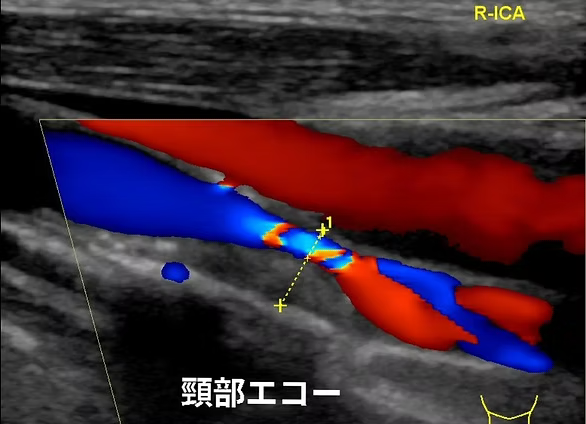

頸動脈エコー、心臓エコー、下肢静脈エコーの検査を行っています。頸動脈エコーは首の中にある頸動脈を観察し、動脈硬化のために血管が傷んでいないか、血液の流れが悪くなっていないかを調べる検査です。心臓エコーは心臓の大きさや心臓の筋肉の動きを観察することによって、心臓のポンプ機能が働いているかを調べます。下肢エコーは太ももからくるぶしにかけて静脈の流れが悪くなってないかを調べる検査です。いずれの検査も痛みのない、手軽で安全な検査です。

頸動脈エコー